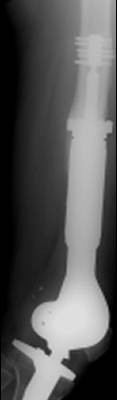

Megaendoprosthesis In The Treatment Of bone Tumors In The ...

From bone cancer in the region of the hip and knee. Remark-able advances in implant technology, surgical reconstructive technique and adoption of new chemotherapy protocols pro-vide a new option for surgeons who diagnose and treat bone tumors. ... Read Document

About surgery for bone cancer 01 About surgery for bone cancer Useful information for cancer patients Contents This information is about the different knee tend to do very well. You may have chemotherapy or radiotherapy after ... Get Doc